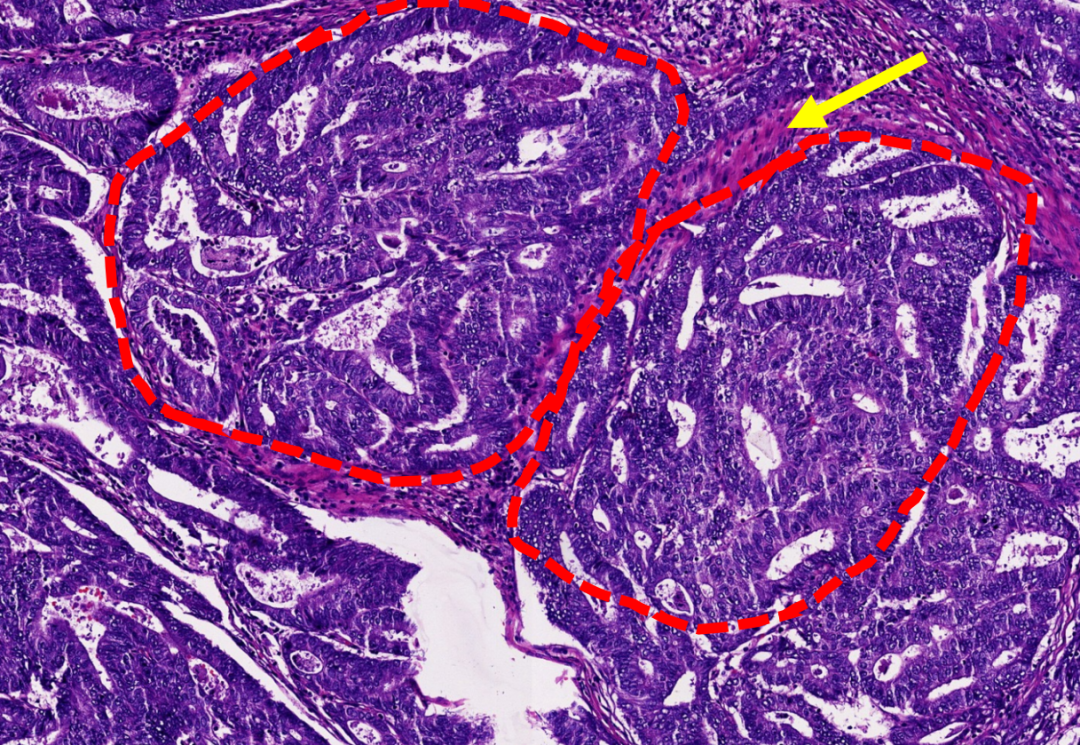

图示:子宫内膜息肉中的厚壁血管簇(红色虚线)。

图示:子宫内膜样癌,腺体结构复杂,融合呈筛网状(红色虚线),间质纤维化(黄色箭头)。